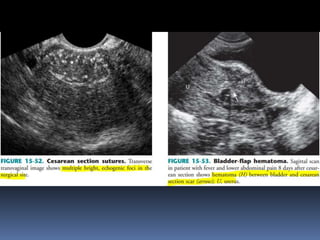

This document contains an image gallery from Dr. Mohit Goel showing various uterine anomalies and ovarian cysts. It includes images of an arcuate and unicornuate uterus, endometritis, a twisted ovarian pedicle, dermoid cysts of varying sizes and echogenicity containing hair, fat, and calcifications, and a combination dermoid cyst showing both mesh and plug structures. The gallery provides ultrasound images of different gynecological conditions for medical education and reference.